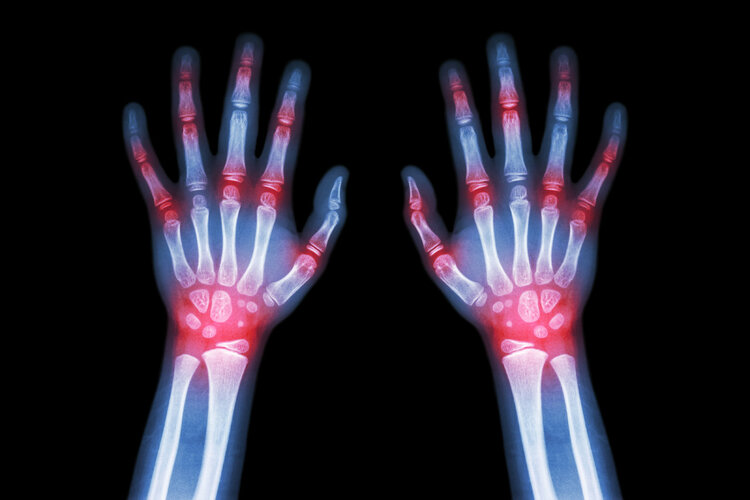

痛风 , 很多人都知道 , 但痛风石就相对了解较少 , 或者受重视程度较低 。 简单来说 , 痛风石就是高尿酸血症没有及时处理 , 导致大量尿酸盐晶体沉积于关节滑膜、软骨及关节周围软组织的结果 。

另外 , 痛风石不受“约束” , 别以为它只会出现在手足部 , 其实它可以游走于全身各个组织 , 包括跖骨的第一跖趾关节、指、腕、肘及膝关节、耳轮等多个部位 , 还有的可长在主动脉、心瓣膜和心肌上 , 简直是“深藏不露” , 很难让人与痛风石联想到一起 , 从而延误治疗 。

广州医科大学附属第三医院关节外科副主任医师张弛提醒:如果痛风石不及时治疗 , 最为直接的后果便是影响患者皮肤外观 , 可导致病灶部位变形;同时还影响患者的日常生活 , 因为血尿酸一直控制不住便会形成尿酸盐结晶 , 具有侵蚀功能 , 可侵蚀骨头 , 导致骨质损毁;严重的会引发皮肤溃烂 , 最终需要截肢保命 , 甚至直接危及生命 。